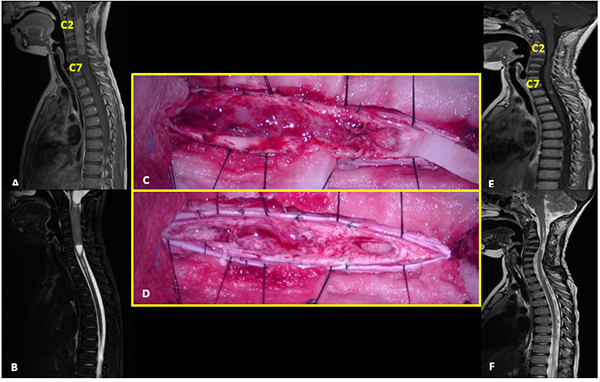

I: Ependimoma

Paciente sexo femenino de 7 años sin antecedentes patológicos de relevancia que consulta por escoliosis y disestesias en miembros inferiores de 6 meses de evolución. Examen neurológico sin déficits motor. En la RM se objetiva extensa lesión intramedular de aspecto infiltrante y bordes poco precisos, extendiéndose desde la unión cérvico-dorsal al nivel D11, predominantemente hipointensa en T1 e hiperintensa en T2, con área de realce anular de aspecto quístico-necrótico a nivel D7. PESS alterados en miembro inferior izquierdo. Se realizó exéresis total de la lesión. El monitoreo neurofisiológico intraoperatorio evidenció episodios de disminución transitoria de la amplitud de la onda D, que revirtieron al detener la exéresis de la lesión. Los PEM no mostraron variaciones significativas. Presentó una paraparesia severa postoperatoria que mejoró progresivamente con rehabilitación. RM control postoperatoria evidencia resección tumoral completa con desplazamiento de lámina de D2 que requirió corrección quirúrgica. La anatomía patológica reveló ependimoma con diferenciación tanicítica focal y células claras. Actualmente sin recurrencia tumoral, en seguimiento estrecho por progresión de escoliosis (Figura 1).

Figura 1: Ependimoma. A-D: RM prequirúrgica T1 con contraste y T2 cortes axiales y sagitales. E-F: Imágenes intraoperatoria pre y postresección. G-J: RM postquirúrgica T1 con contraste y T2 cortes axiales y sagitales.